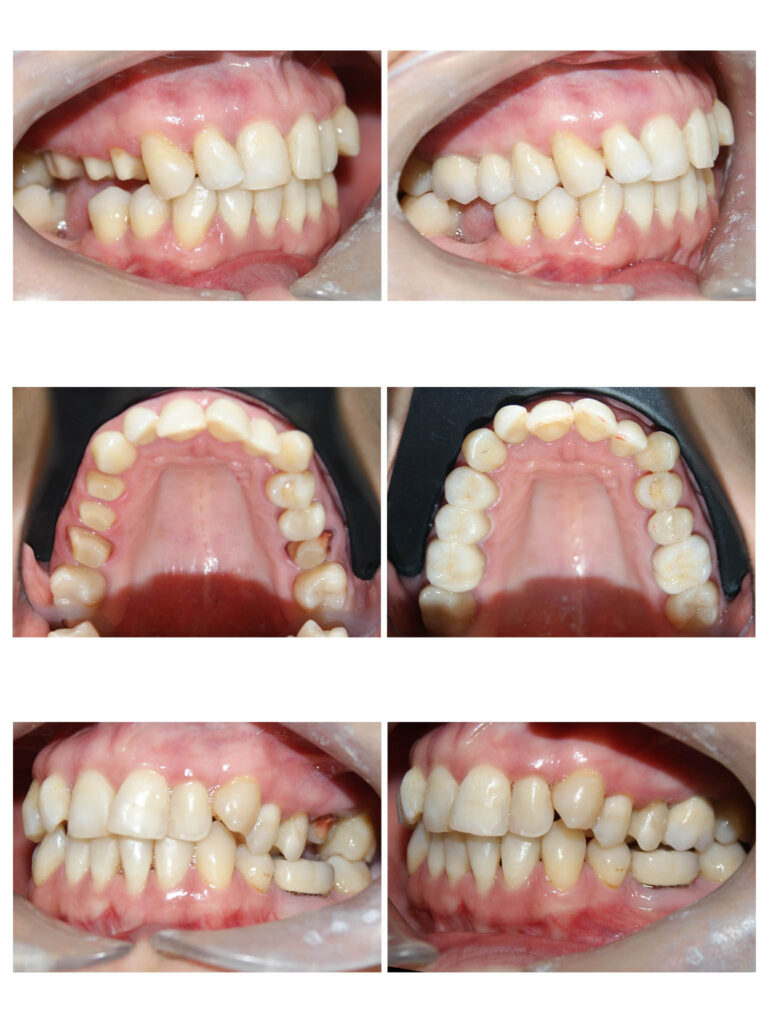

Întrebare “Ce se întâmplă dacă îmi vor fi extrași dinți buni? “Răspuns “Spațiile vor fi închise complet! “ DA, DA, DA! Adesea trebuie să facem extracții în scop ortodontic pentru a crea spațiul necesar alinierii dinților care rămân pe arcadă. În aproximativ 2 ani de tratament ortodontic dinții migrează și închid spațiile astfel încât vei uita că acolo au mai fost vreodată alți dinți